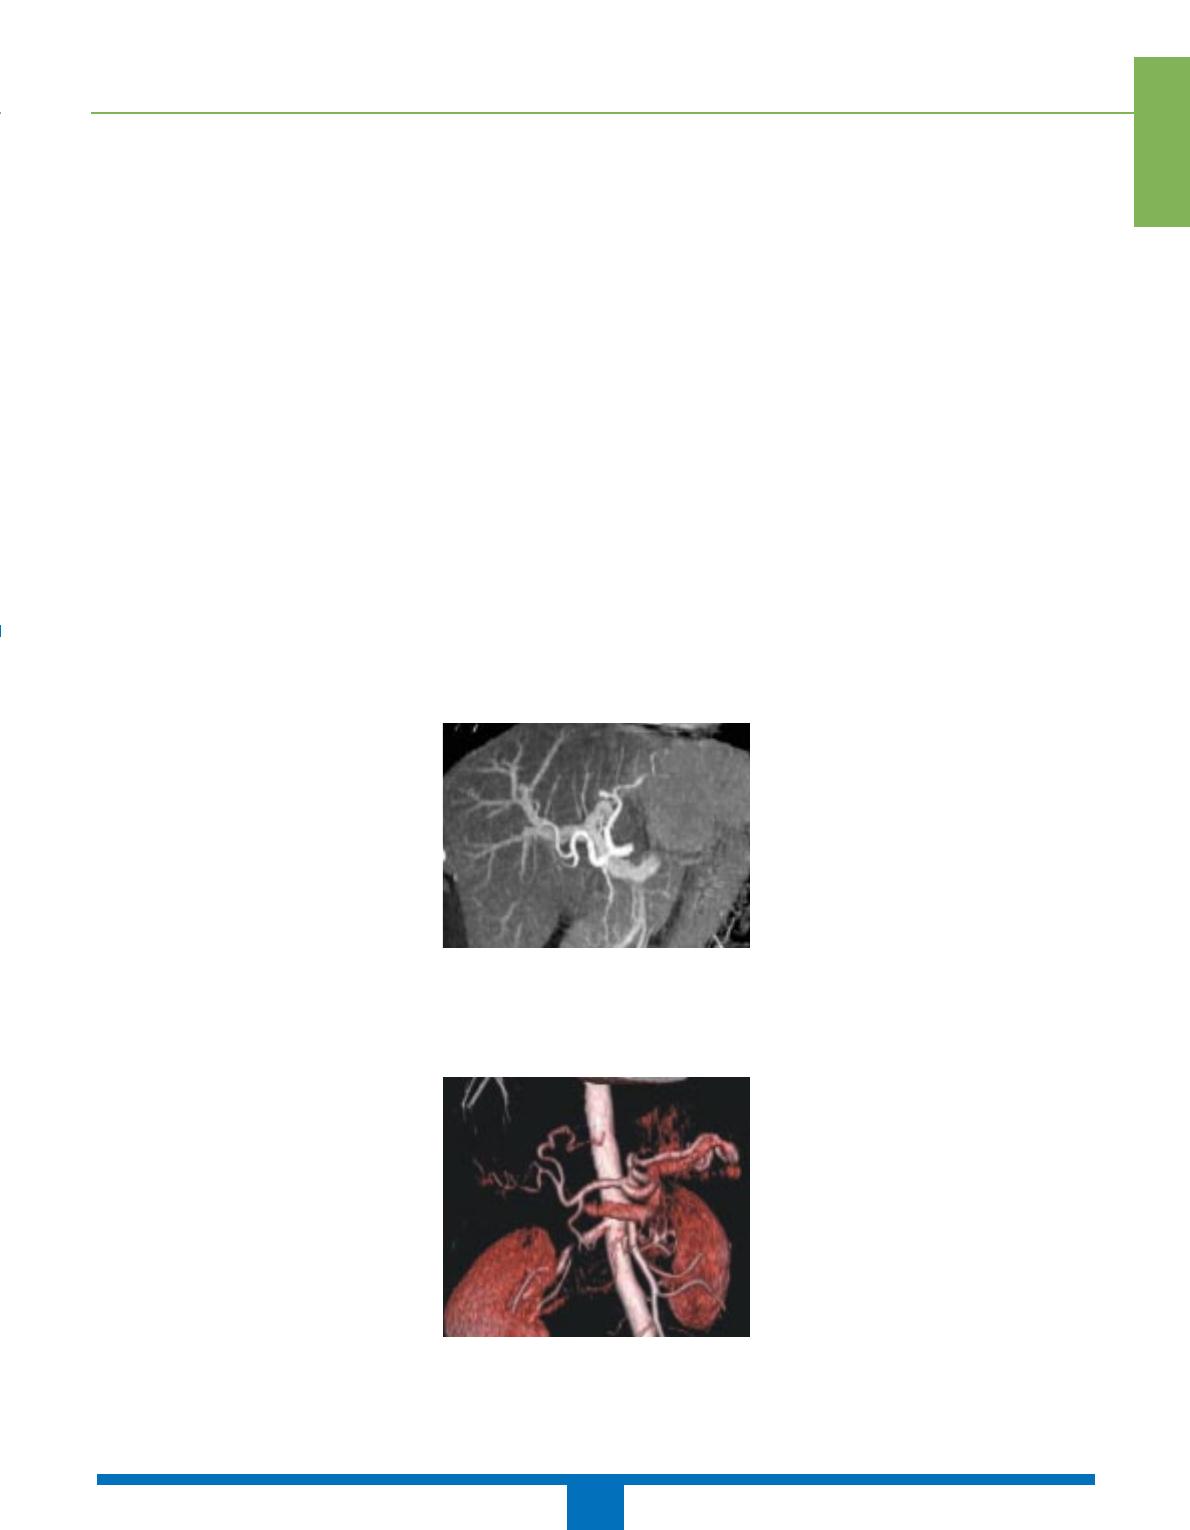

Les coupes acquises sont examinées

dans le plan axial natif, mais peuvent

aussi faire l’objet de reconstructions

multiplanaires vasculaires de type MPR

[multiplanar reformation],MIP [maxi-

mum projection intensity] (figure 1) et

3D VRT [volume-rendered technique]

(figure 2). Les plans de reconstruction

sont le plus souvent axiaux ou coro-

naux, mais peuvent être adaptés selon

l’anatomie de chaque patient et les ano-

malies repérées sur les coupes natives.

Les reconstructions MIP et VRT per-

mettent ainsi de visualiser préférentiel-

lement les vaisseaux par rapport aux

structures tissulaires adjacentes, don-

nant des images qui se rapprochent de

celles obtenues en artériographie.

Figure 1. Reconstruction en technique MIP

à partir de coupes scanographiques mon-

trant la vascularisation artérielle et portale

du foie chez un donneur vivant avant prélè-

vement.